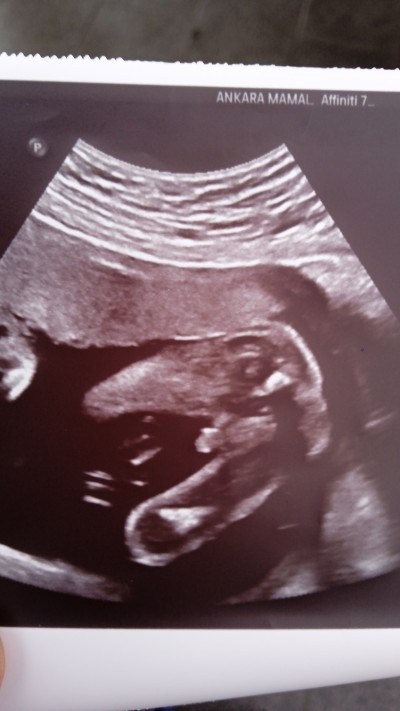

ben burdayım diyor ama içimden kız geçiyor kız hissediyorum bu resme ragmen😆tabi sağlıklı olsun cnm oğlum

Kaç haftalık bu resimde? baya görünüyor erkek olduğu sağ salim alasiniz kucağıniza benimde 2 kız 1 oğlum var oğlum felç olduğu için yürümüyor o yüzden çok istiyoruz erkek kısmet

Rabbim sağlık sıhhat versin inşallah burda 20.hafta